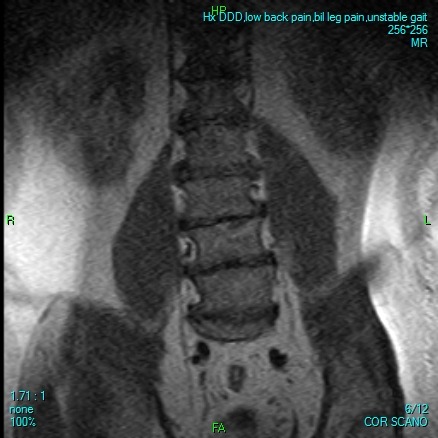

Some days he can barely stand or walk a few steps without collapsing in agony. Many nights, he lies alone, tears streaming down his face, praying for relief. His doctors have been clear: without urgent spinal surgery, he faces the devastating reality of becoming completely bedridden—possibly forever.

Desperate for relief, he trusted a foreign clinic that promised affordable treatment. Instead, they took advantage of him, leaving him stranded far from home in Mexico with no money to return. After months of struggle, honest and ethical doctors here in North America confirm they are prepared and able to perform the surgery he urgently needs. But the hospital requires $17,600 upfront to cover his Medicare deductible and uncovered costs before they can even admit him.